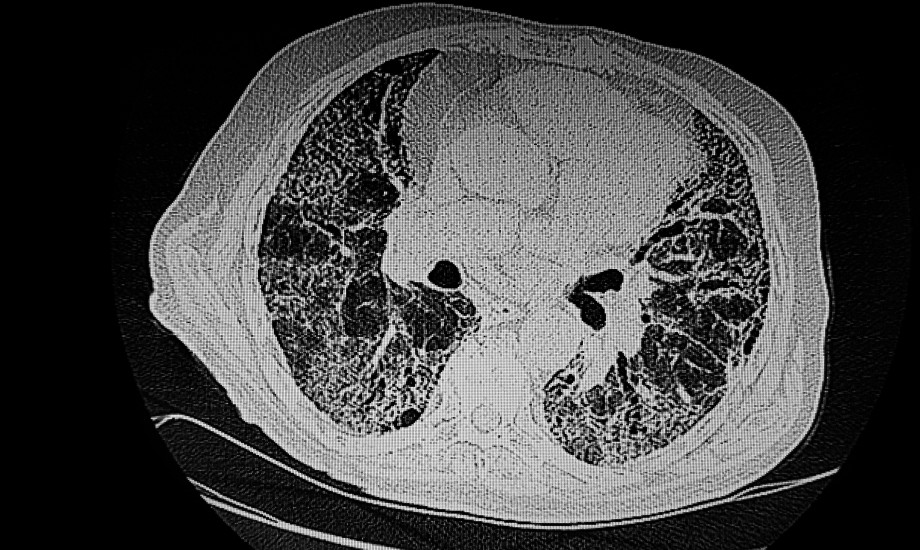

Idiopathische Lungenfibrose

Die Leitlinie Idiopathische Lungenfibrose, die unter der Federführung der DGP entstanden ist, wurde erstmals seit 2017 aktualisiert. Der Umfang der wissenschaftlichen Erkenntnisse habe in einem deutlichen Maße zugenommen, sodass die Aktualisierung nur den Bereich der Diagnostik betreffe und als Ergänzung zur ursprünglichen Leitlinie veröffentlicht werden.